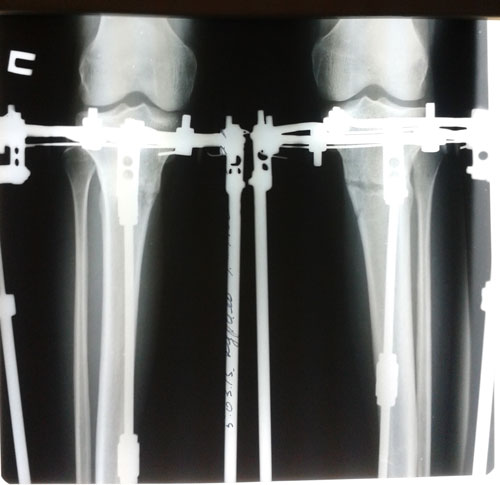

рентген в 86 дней после операции.

Пора на снятие аппаратов! 36a50961607